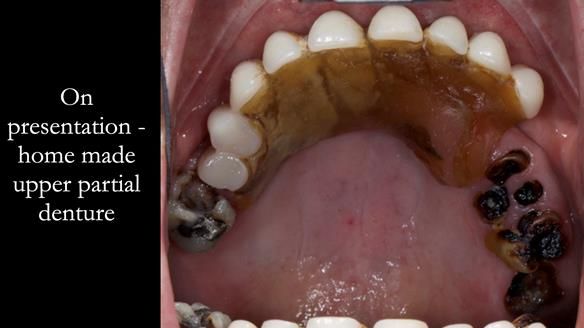

Bad dental experiences over 20 years ago had put Jo off from visiting the dentist. She had resorted to replacing her missing upper front teeth by making a partial denture using artificial teeth and a base made from artificial acrylic nail powder/liquid kit, purchased on the internet. She had recently explored the possibility of immediate load dental implant supported teeth.

- The missing upper front teeth are replaced by a denture made by the patient. This has poor fit and appearance.

- The upper ridge with missing teeth has very little underlying bone.

- The upper natural teeth have hopeless prognosis due to dental caries.